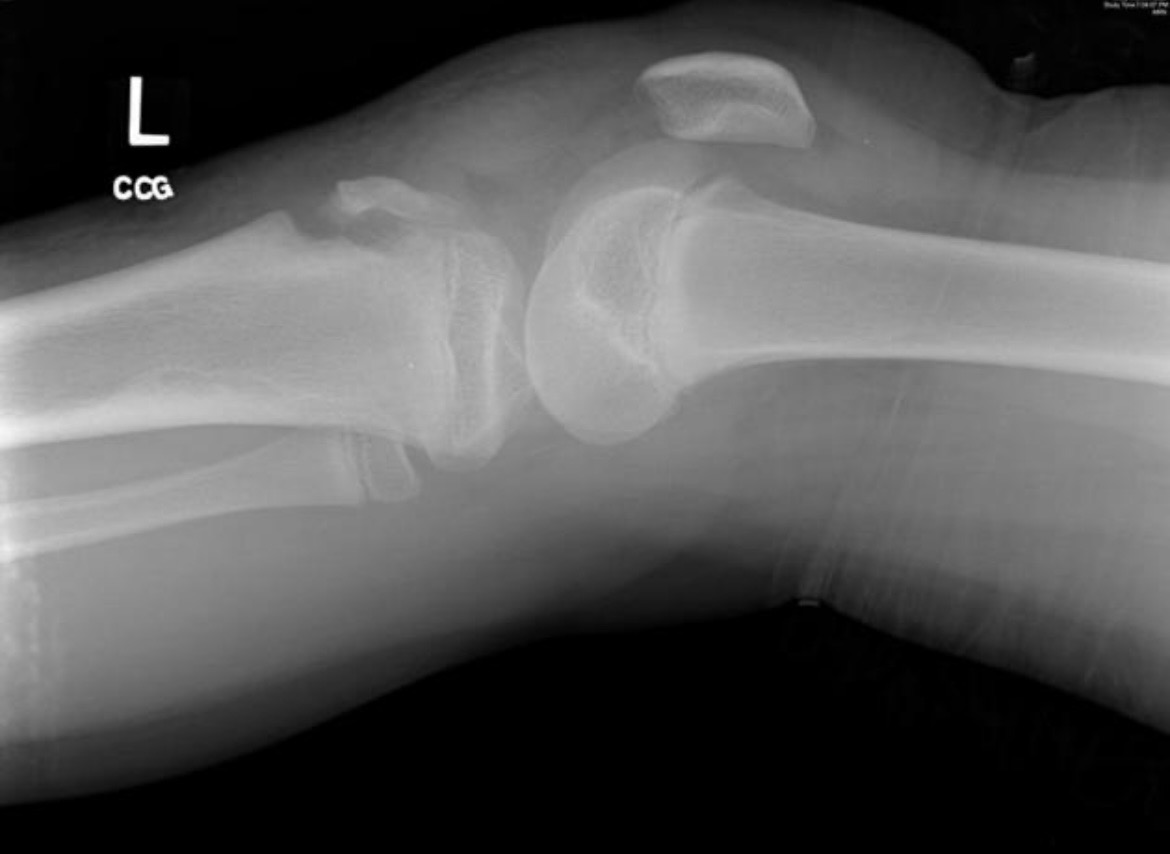

4. Tibial tuberositas avülsiyon fraktürü

- Kas bağlantısı: Patellar tendon (Quadriceps)

- Mekanizma: Sıçrama, basketbol smacı, voleybol

- Klinik: Diz önünde ani ağrı, hematom

- Sporcu tipi: Basketbolcu, voleybolcu

- Direkt grafi: İlk tercih. Avülsiyon hattı, kemik parçasının yer değiştirmesi görülebilir.

- BT: Karmaşık eklem içi avülsiyonları değerlendirmede faydalıdır.

- MRG: Küçük parçaların saptanması, tendon/bağ yırtıklarının değerlendirilmesi için gerekebilmektedir8.